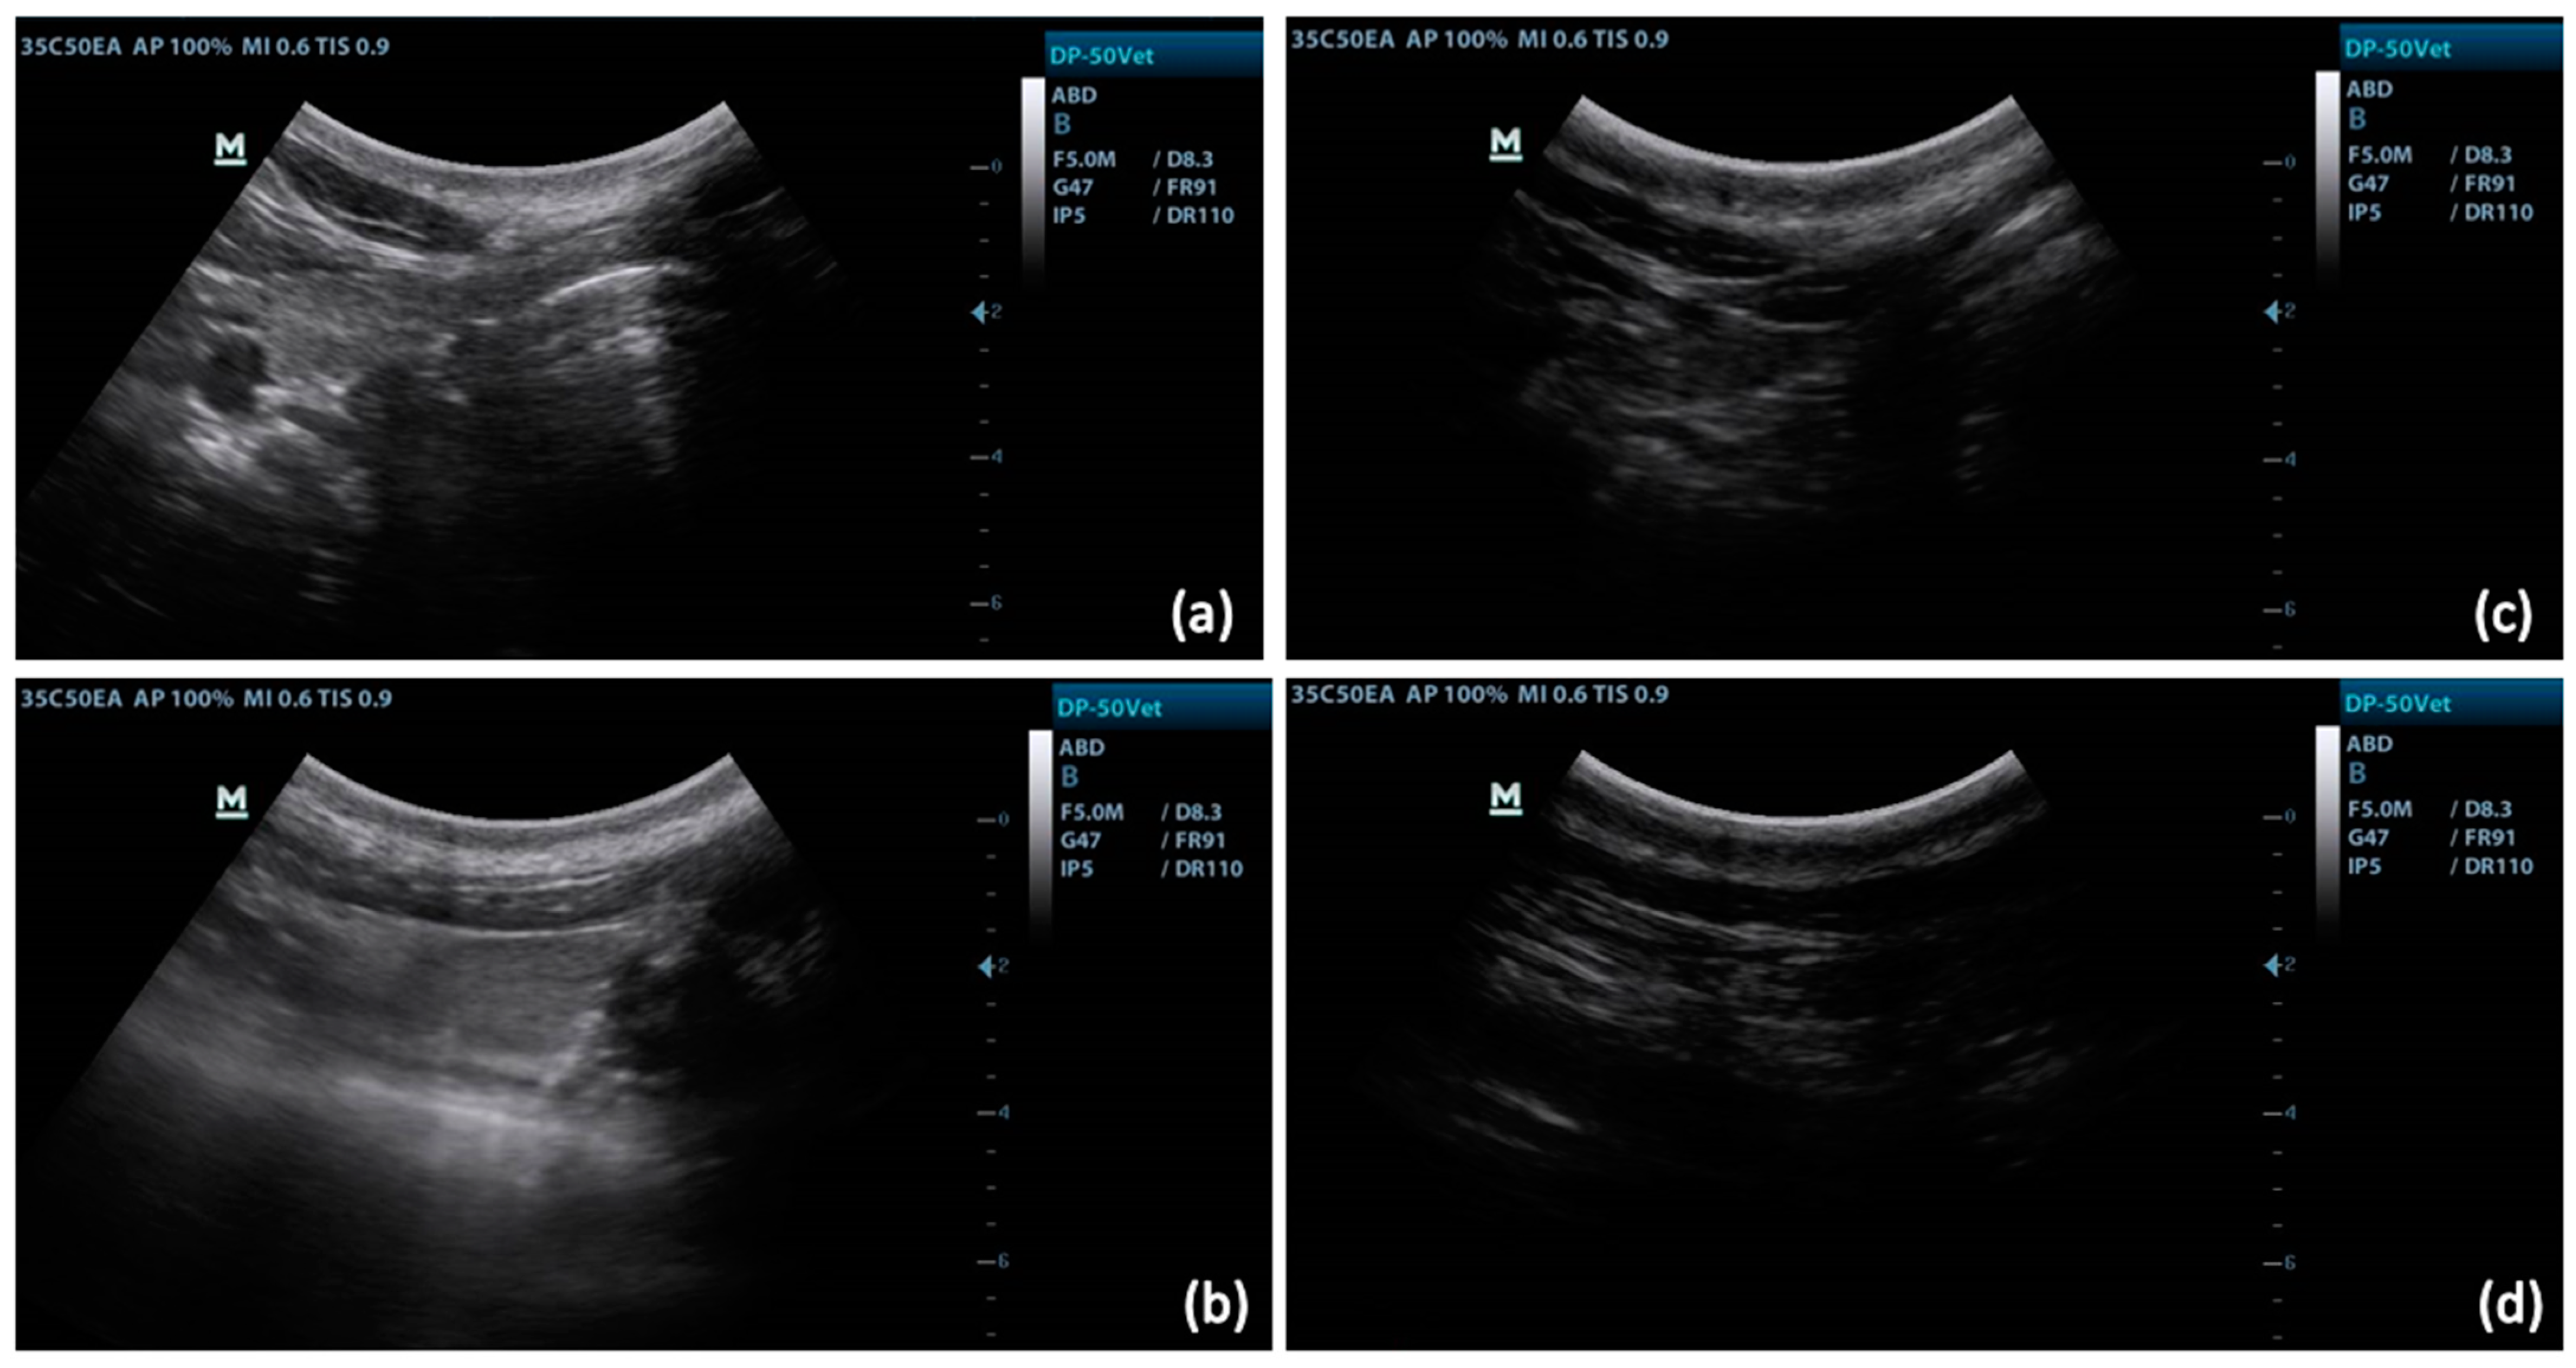

3.1. Ultrasound Technique and Measurements